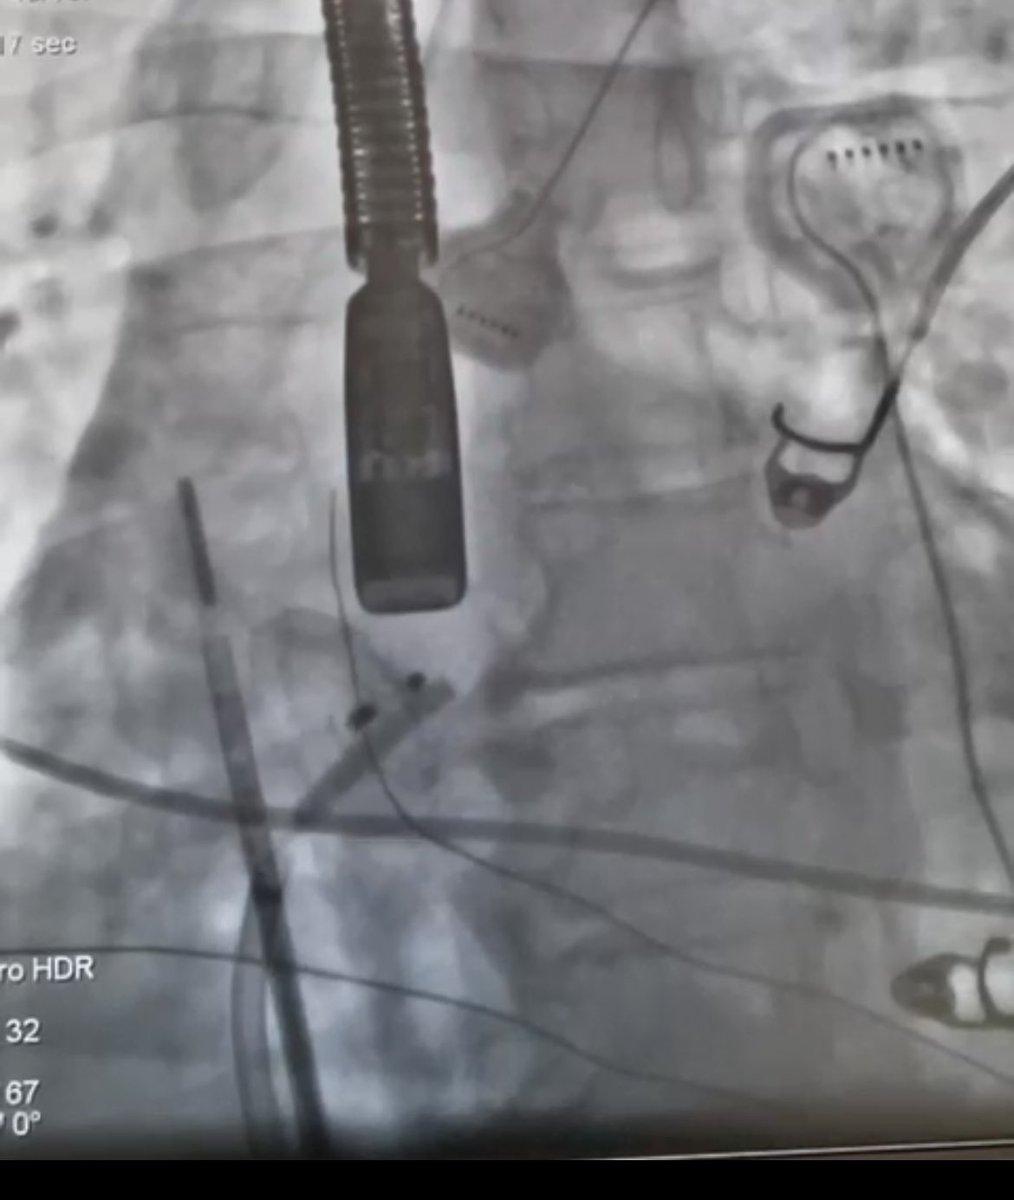

45yo male, STEMI in 2016 w/ late reperfusion, DAPT, apical aneurysm, history of apical thrombus, LVEF 42%, thrombus not mentioned. ER admission due to electrical storm. EPS w/ LV apical VT 320ms CL. ICE sees the following image in EPlab. What'd you do? #epeeps #ablateVT #ICEeyes

LV apical VT. LV apical thrombus demanded cerebral protection with Sentinel filter. #epeeps #CardioTwitter #ablateVT #ICEeyes #VThunter #EnsiteX #abbottproud SOBRAC Abbott Cardiovascular Abbott SBC Científico Socergs